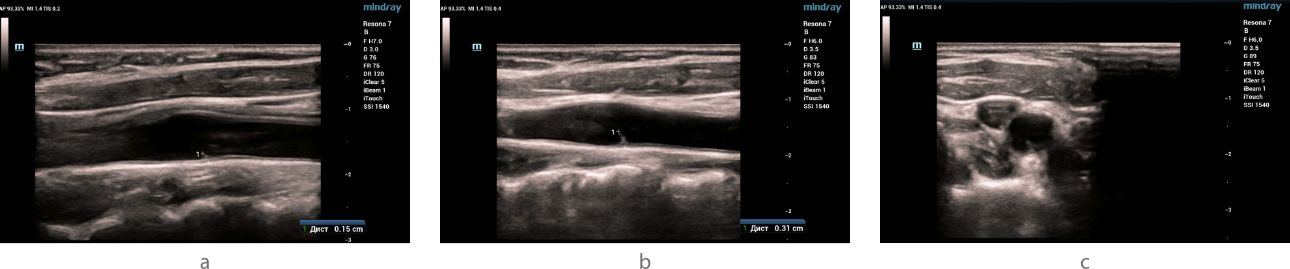

Ultrasound examination - B- mode

Ultrasound examination (ultrasound) of the carotid and vertebral arteries was performed on the Resona 7 ultrasound machine (Mindray, China) using the L9-3U linear probe. When examined in B-mode in the area of bifurcation of the common carotid artery, a hyperechoic linear structure (slightly expanding at the base) with clear even contours, without signs of flotation, having a slope towards the internal carotid artery and protruding into the lumen of the vessel was visualized on both sides along the posterior wall: on the right by 1.5 mm, on the left by 3.1 mm (fig. 1). No structural changes were detected in other carotid and vertebral arteries.

aotid-web-v-flow-fig1-pc

Fig 1. Ultrasound of the carotid sinus in B-mode.

In the bifurcation of the common carotid artery, markers indicate a linear hyperechoic signal with dimensions on the right (a) and left (b) in the longitudinal scanning plane. The type of hyperechoic signal (indicated by the arrow) in the left common carotid artery in the transverse scanning plane (c).